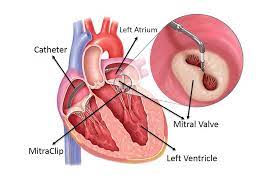

Overview

Package includes:

Days in hospital : 7 to 8 Days (For patient and one attendant)

Days in hotel : 12 Days (For patient and one attendant)

Room type in hospital : Shared

Room type in hotel : Private

Hotel category: General

Value added benefits of the Mitral Valve Replacement:

Ø Doctor consultation charges

Ø Lab tests and diagnostic charges

Ø Room charges inside hospital during the procedure

Ø Surgeon Fee

Ø Cost of implant

Ø Nursing charges

Ø Hospital surgery suite charges

Ø Anesthesia charges

Ø Routine medicines and routine consumables (bandages, dressings etc.)

Ø Food and Beverages inside hospital stay for patient and one attendant.

Extra benefits:

ü Interpreter

ü Visa assistance

Ø Site tourism of the city

Ø Follow up with the doctor

Ø Airport pick up and drop

Ø Free online consultation with the doctor

Ø Priority appointments with the doctor

Ø Room upgrade from sharing to private